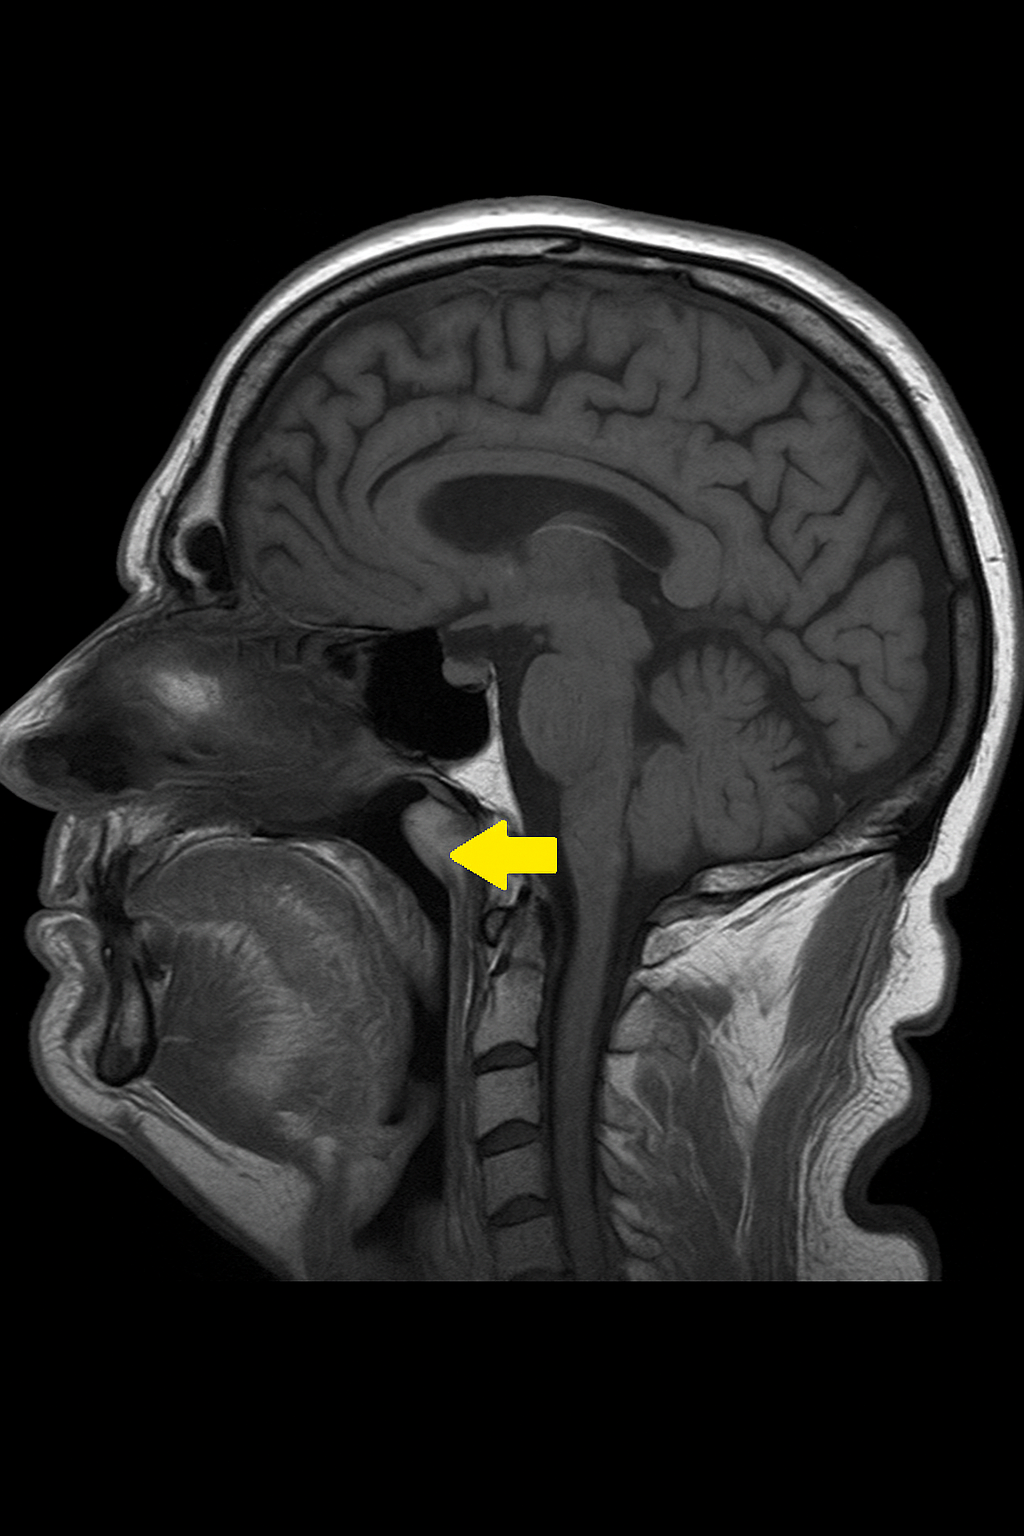

- Manyetik Rezonans Görüntüleme (MRG): Yumuşak doku çözünürlüğü yüksek olduğu için tercih edilir. T2-ağırlıklı sekanslarda hiperintens kistik lezyon izlenir.

Tornwaldt kistleri genellikle nazofarenksin dorsal orta hattında, üst servikal omurga düzeyine yakın yerleşim gösterir. Kistin duvarı genellikle kalınlaşmıştır ve içi mukoid materyal ile doludur. Enfekte formlarında içerik pürülan hale gelir. Histolojik olarak kist duvarı respiratuar tipte silyalı psödostratifiye epitel ile döşelidir ve çoğu zaman kronik inflamatuar hücre infiltrasyonları gözlenebilir.